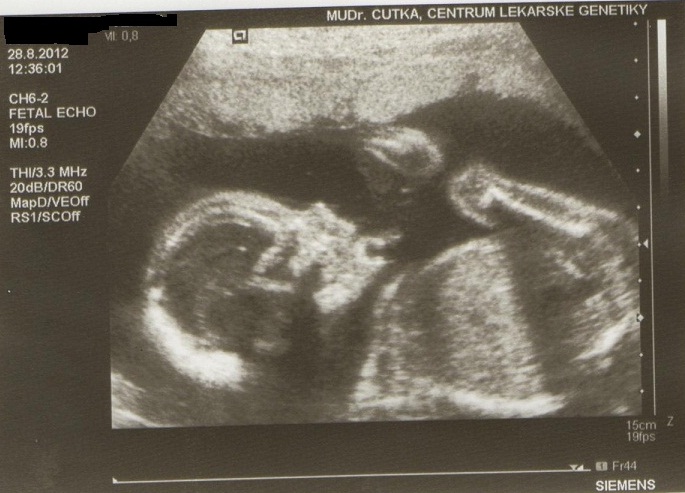

Holky přidávám fotečky naší malinké z minulého týdnu z velkého utz. Dostali jsme tři na dvou je skoro celá a na jedné je záběr na pusinku.